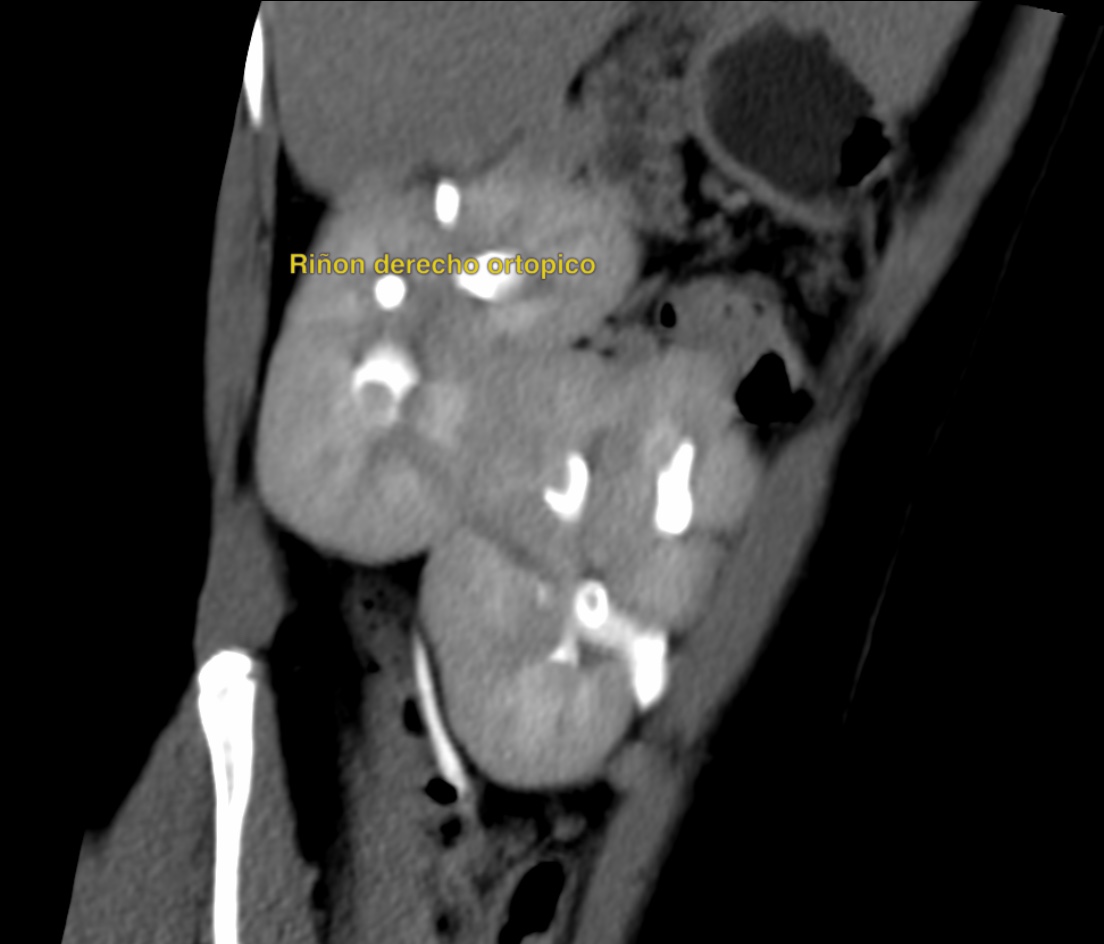

Caso #1: Ectopía Renal Cruzada Fusionada

Paciente femenina en la que se identificó ausencia de riñón izquierdo en fosa renal, con fusión renal en flanco derecho. Las reconstrucciones 3D y cortes axiales confirman una ectopía renal cruzada tipo A con malrotación de ambos riñones. Cada uréter conserva su trayecto anatómico hacia su meato correspondiente en vejiga.

Corte axial TC Reconstrucción 3D 1 Reconstrucción 3D 2 Plano sagital VR uréteres